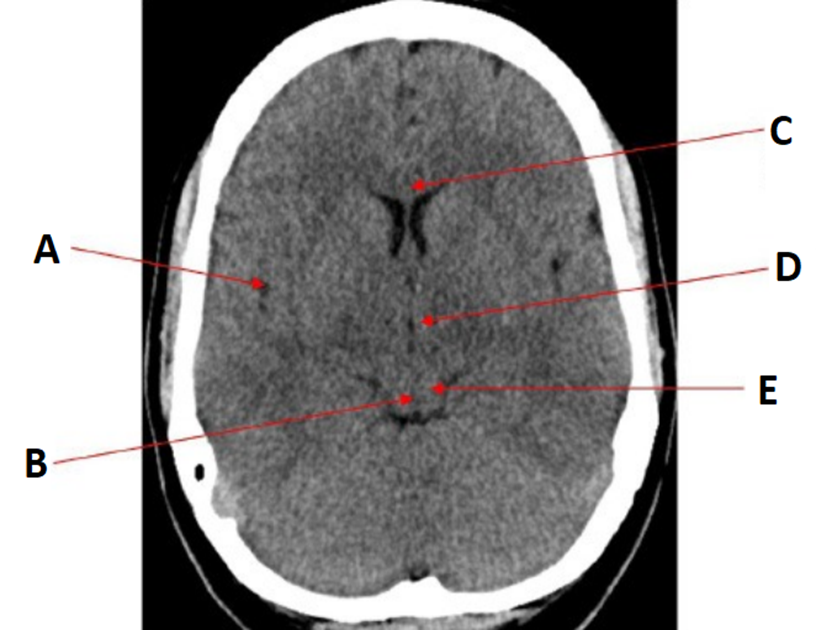

label

•A = Basilar artery

•B = Pons

•C = Fourth ventricle

•D = Frontal sinuses

•E = Middle cerebral artery

•F = Mastoid air cells